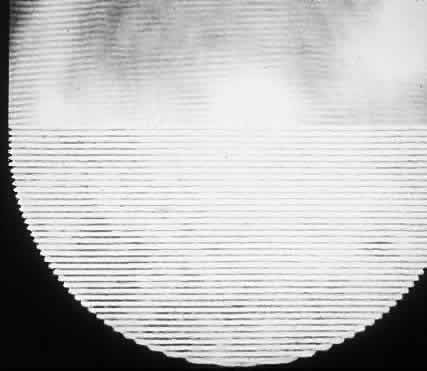

much smaller than a wavelength of yellow light (600 nm).4 Thus, the tiny dimensions and regular arrangement of these fibrils (Fig. 5) account for the minimal scattering.  Fig. 5. Top. Electron micrograph shows the arrangement of collagen fibers in normal

corneal stroma. Bottom. Electron micrograph of a corneal stroma with edema. Note the irregular

collection of fluid. (Miller D, Benedek G: Intraocular Light Scattering. Springfield, IL, Charles

C Thomas, 1973. Courtesy of T. Kuwabara, Howe Laboratory, Harvard

Medical School) Fig. 5. Top. Electron micrograph shows the arrangement of collagen fibers in normal

corneal stroma. Bottom. Electron micrograph of a corneal stroma with edema. Note the irregular

collection of fluid. (Miller D, Benedek G: Intraocular Light Scattering. Springfield, IL, Charles

C Thomas, 1973. Courtesy of T. Kuwabara, Howe Laboratory, Harvard

Medical School)

CORNEAL STROMAL EDEMA In cases of endothelial dystrophy, endothelial trauma, or endothelial incapacitation

due to inflammation (i.e., iritis), the pumping action of the endothelium diminishes and the stroma

takes on additional fluid and thickens. As interfibrillar fluid increases, the

collagen fibers are pushed farther and farther apart. As

the lakes of such fluid exceed one half of a wavelength of light in dimension, light

scattering increases and the cornea takes on a gray appearance (see Fig. 5).4 CORNEAL EPITHELIAL EDEMA In cases of advanced endothelial impairment or acute glaucoma, fluid collects